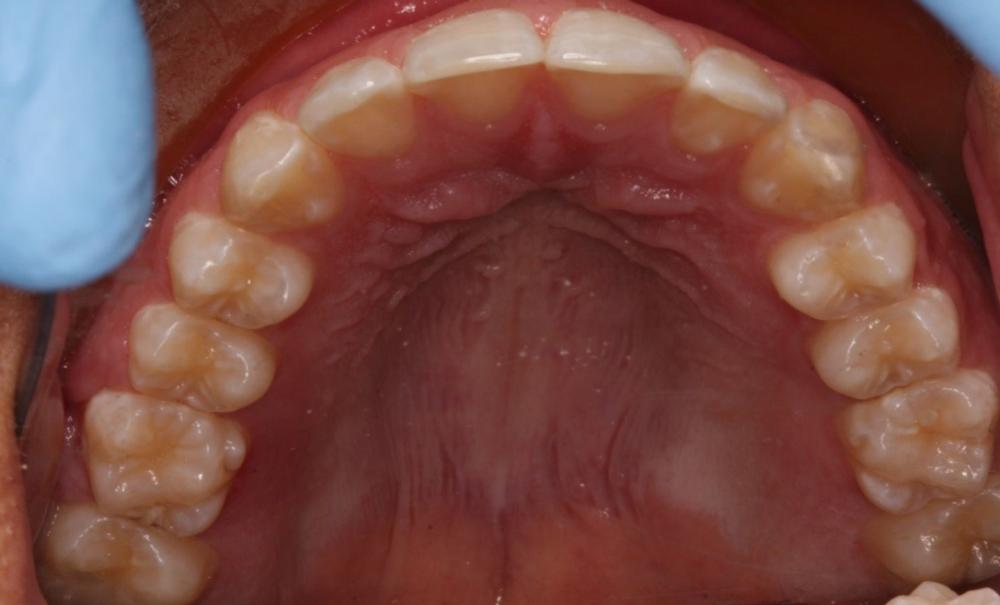

Narrow arch before RME

Presents as/What to look for: It’s most common when a child has a posterior crossbite, when the top teeth fit inside of the bottom teeth (normally the top teeth bite outside the lower teeth) and also in cases of severe crowding. Sometimes, due to the positions of the jaws, there isn’t a crossbite but the upper jaw is too narrow to fit well around the lower jaw when they are in good positions, but this is really only something that a dentist can measure.

Complications: This can result in crowding and misalignment of the teeth as not every child has enough space in their jaw for all their adult teeth. It can also limit the position of the lower jaw and the way the mouth closes